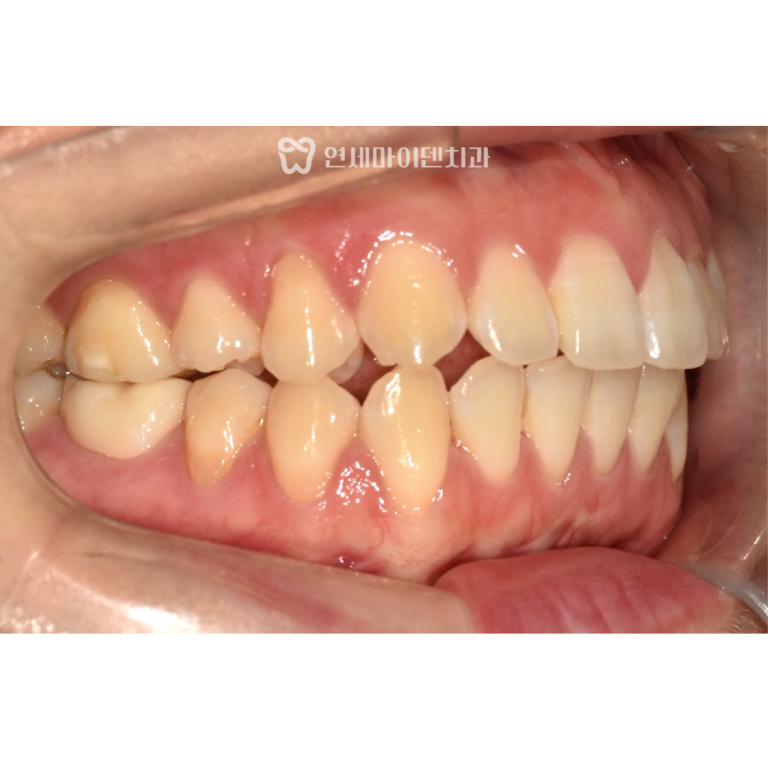

안녕하세요, 소중한 치아를 지키는연세마이덴치과입니다. 이번 증례는 심한 부정교합과 덧니가 있던30대 환자분의 비발치 교정 케이스입니다. 좁은 악궁을…